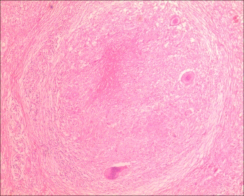

1.常规病理诊断(病理组织形态特征):结核病是一种特殊类型的慢性肉芽肿炎,基本病理变化:渗出、增生、坏死,典型病变形成结核结节,结节中心为干酪样坏死,坏死周边围绕类上皮细胞、散在多少不等的

Langhans巨细胞,结节外侧为淋巴细胞及少量反应性增生纤维母细胞。